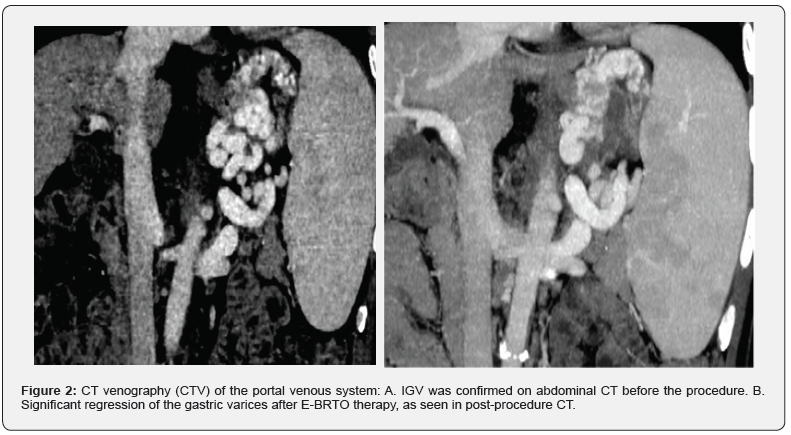

A 5.5F balloon occlusive catheter was introduced into the hepatic vein through the right internal jugular vein or the right femoral vein. The wedge pressure of the hepatic vein was measured after balloon occlusion of the hepatic vein. The free pressure of the hepatic vein and the inferior vena cava pressure were measured after removal of the occlusion. Finally, the Hepatic Vein Pressure Gradient (HVPG) was calculated. Angiography was performed to visualize the prominent GRS and IGV (Figure 1B). According to the diameter of GRS, a balloon catheter with appropriate size was selected to block the GRS. The balloon occlusive catheter was introduced into the shunt and inflated to occlude the GRS (Figure 1C). Repeat angiography was performed to evaluate the position and size of the IGV (Figure 1D). The patient was placed in a left lateral position and the vital parameters of the patient (including heart rate, respiratory rate, oxygen saturation, and blood pressure) and electrocardiogram were continuously monitored preoperatively. Endoscopic examination was conducted to confirm the presence of GV and the volume of the varices (Figure 2A). Histoacryl was injected into the GV at multiple points. Each injection was performed with the “sandwich technique” i.e. 1.5mL Histoacryl was sandwiched between two doses of 2mL 50% glucose solution depending on the volume of the needle (Figure 2B). After each injection location, a satisfactory result was defined as hardening of the varices on gentle probing of the varices using a needle catheter. At the end of the procedure, before removing the balloon catheter, a repeat angiogram was performed to confirm the resolution of the IGV (Figure 1D). The therapy was defined as successful if the blood supply of the IGV was completely obliterated. The balloon occlusive catheter was then deflated and removed.

Antibiotics were routinely administered for 5-7 days after the procedure [17]. Post-treatment repeat radiological imaging was conducted to observe the varices if any remained (Figure 3A). Re-examination by endoscopy was also performed to confirm the resolution of the IGV (Figure 3B, 3C,3D), indicating successful treatment. A detailed operative note for each patient was carefully recorded. Repeat endoscopic examinations and follow-ups were performed after the E-BRTO procedure to identify complications, residual varices, recurrence, re-bleeding, aggravation of EV, and survival rates.